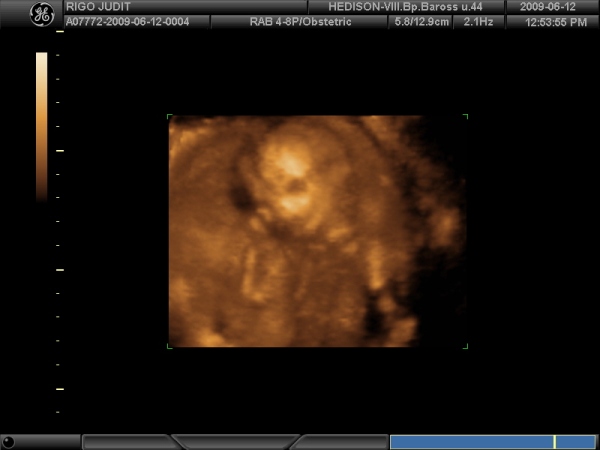

Kismór is jól beletemette az arcát a méhlepénybe, de a kukit azt büszkén mutogatta, úgyhogy Bogyi valószínűleg kislány, mert csak a férfiak tudnak ilyen büszkék lenni a nemiszervükre:I))